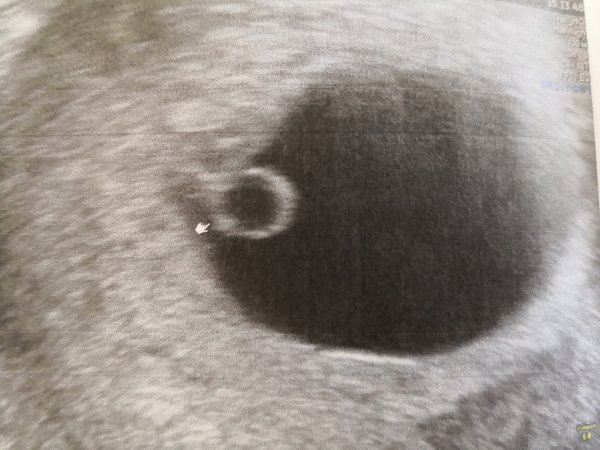

Jippi! Den lille lever hvertfall enn så lenge ❤️Hjertet slo og den ble målt til å være 6+0 slik menstermin også tilsier - god start hvertfall! Står at termin er 31.januar! Nå kan jeg sette litt mer pris på den stadig økende kvalmen!

IMG_20190607_153303.jpg